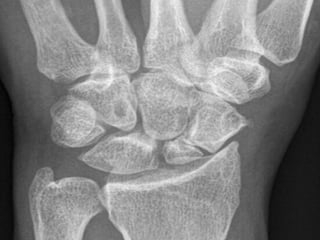

Radiography

 The 4 essential views (ie, PA, lateral, supinated and

pronated obliques) identify majority of fractures.

 The scaphoid view is a PA radiograph with the wrist

extended 30° and deviated ulnarly 20°. This view

helps to stretch out the scaphoid and is also used for

assessing the degree of scaphoid fracture angulation.

 A clenched-fist radiograph has also been useful for

visualization of the scaphoid waist.

Radiography  The 4essential views (ie, PA, lateral, supinated and pronated obliques) identify majority of fractures.  The scaphoid view is a PA radiograph with the wrist extended 30° and deviated ulnarly 20°. This view helps to stretch out the scaphoid and is also used for assessing the degree of scaphoid fracture angulation.  A clenched-fist radiograph has also been useful for visualization of the scaphoid waist.